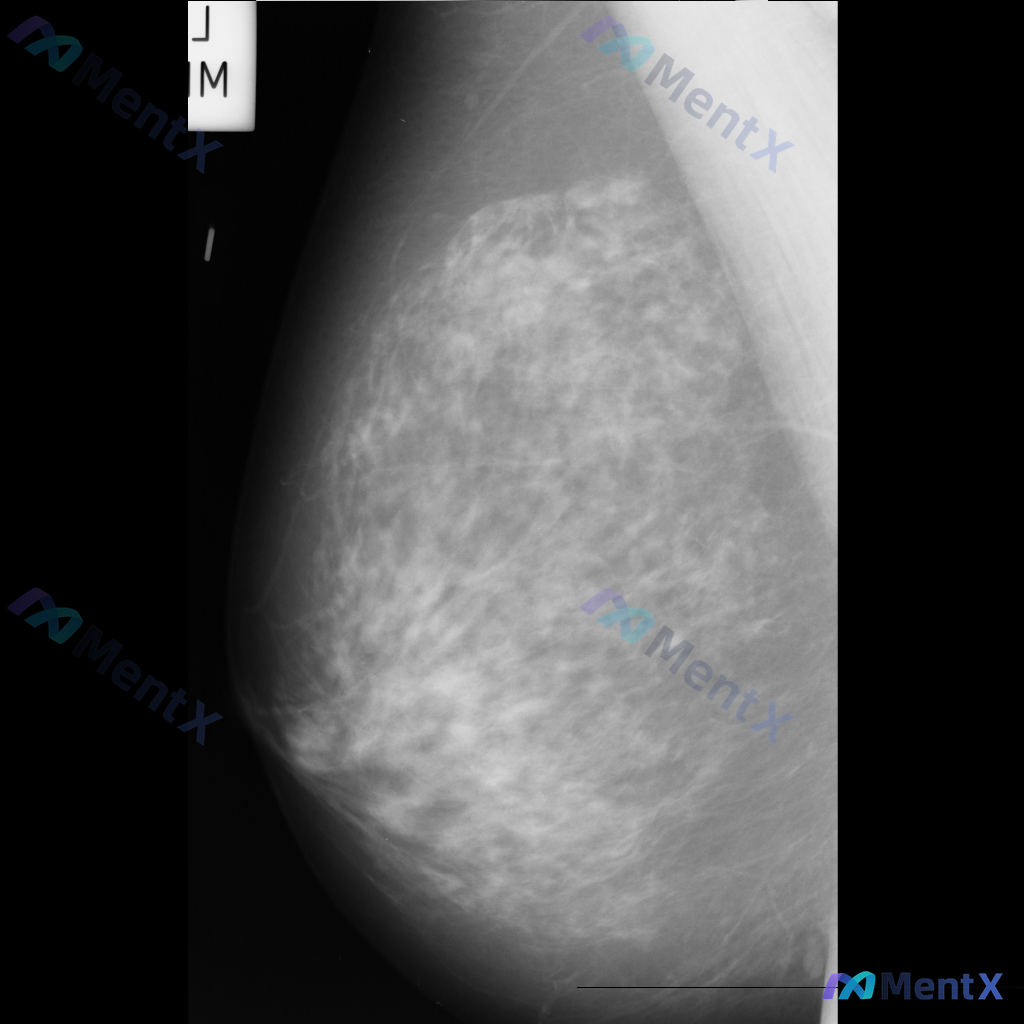

这张左乳钼靶影像,大家看核心异常更倾向哪种情况?

整理到一份乳腺钼靶的影像讨论资料,先和大家同步一下基本信息: - 检查部位:左乳 - 投照体位:内外斜位(MLO) - 影像表现: 1. 左乳外侧偏上象限可见不规则高密度肿块影 2. 肿块边缘模糊,部分区域有毛刺样改变 3. 肿块周围存在局限性结构扭曲 目前先不补充更多信息,想听听大家的第一判断:这...